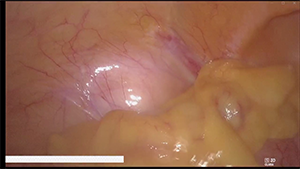

腹腔镜辅助全胃切除(D2淋巴结清扫)伴食管空肠吻合术

作者:高飞 | 作者单位:郑州大学第二附属医院